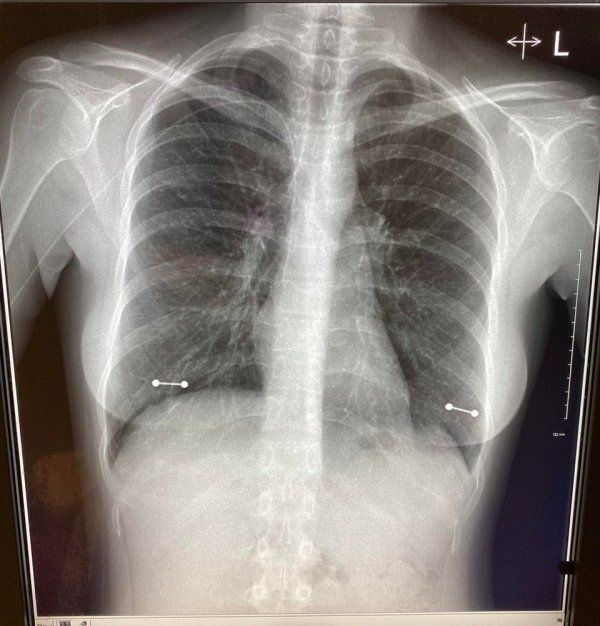

Девушка забыла снять пирсинг во время прохождения рентгена. Украшения и пирсинг можно не снимать во время рентгеновского обследования, если у вас они сделаны из качественного имплантационного титана.